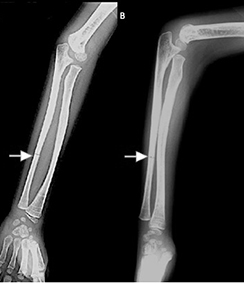

Figura 3 (A, B) Fractura transversa del tercio medio de la diáfisis del cúbito derecho en niño de 6 años de edad, con OI tipo III, tras 4 años de tratamiento con bifosfonatos.

Figura 3